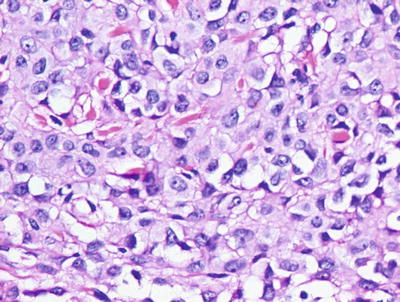

Fig. 20.1

Lentigo simplex has elongated rete ridges and increased basilar melanin . There are essentially normal numbers of melanocytes present in the epidermis. Sun damage is not present in the underlying dermis